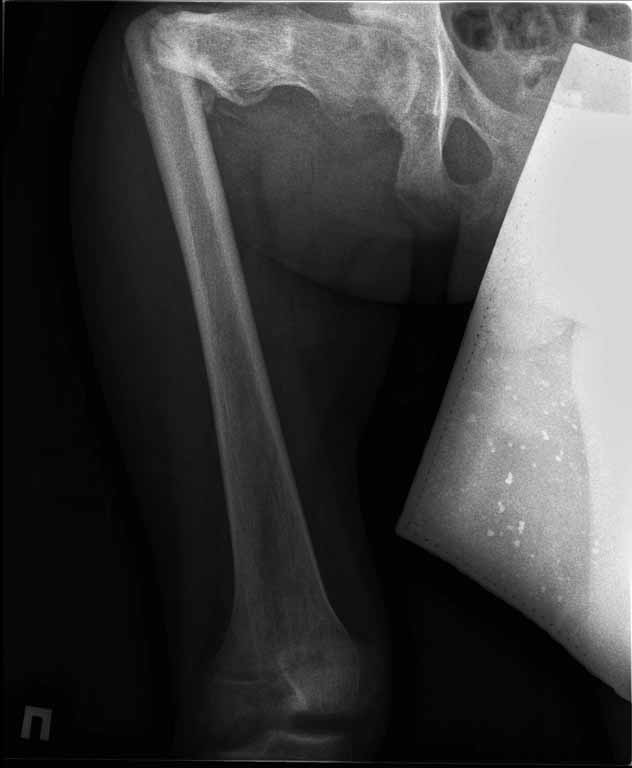

Пациенту 22 года. Травма в июле 2010г, лечился в районной больнице. К нам попал в апреле 2011г.Тяжелая сочетанная травма (29.07.2010): тупая травма живота с повреждением внутренних органов. Закрытая травма грудной клетки с переломом ребер. Пневмоторакс справа. Тяжёлая позвоночно-спинномозговая травма. Закрытый осложнённый переломо-вывих С5 позвонка. Верхний парапарез, нижняя параплегия, нарушение функции тазовых органов по типу недержания. Цекостома. Пролежень левой ягодичной области. Неправильно консолидированные переломы верхних третей обеих бедер. Застарелый вывих левого бедра.Осложнение: Поддиафрагамльный абсесс слева, забрюшинного пространства. Свищ желудка и ободочной кишки. Синегнойный сепсис. Двухстороняя пневмония. Но это уже анамнез.Пациент был неоднократно оперирован на органах брюшной полости и осложнениями с ними связанными.

В ягодичной области слева глубокий пролежень размером 2х2см, дном является вывихнутая головка бедра. Неврологически в нижних конечностях динамика положительная, появились движения в правой стопе, чувствительность в стопах.По переломам бедер: подвижности в местах переломов нет, снимки высылаю.

Уважаемые коллеги, помогите определиться с оптимальной тактикой в лечении перелома бедер. Степень оснащенности у нас достаточная (аппараты, штифты, пластины, ЭОП).